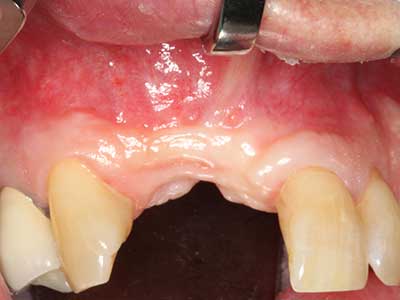

Fig. 2: Defecto del maxilar superior lateral vertical y horizontal con línea de la sonrisa alta, con indicación para la reconstrucción antes del implante.

Fig. 3: La separación basal del bloque se ve facilitada con piezas dotadas de una angulación especial.

Fig. 21: Defecto extendido del incisivo superior con indicación para osteogénesis de distracción con tejido blando cicatrizado después de una operación previa.